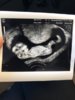

Jeg har hatt to missed abortions hvor den første ble oppdaget i uke 14 hvor jeg tenkte alt var ok. I andre graviditet kom jeg i uke 6 hvor de sa det var en blighted ovum eller gravid utenfor livmor. Så gynekologen fortsatte å følge meg opp i tredje graviditet. Hadde jeg ikke fått det (må ikke betale) hadde jeg uansett tatt tidlig ultralyd og betalt for det. Det er spennende å følge med at alt går bra, en trygghet, jeg er spent på om babyen ser frisk ut. Dersom f.eks babyen har alvorlige koromosomfeil el. vil jeg vite det så tidlig som mulig for å bestemme hva jeg ønsker å gjøre. Ærlig talt kan jeg ikke helt forstå folk som ikke tar tidlig ultralyd, men det er nå meg - skadet av mye kjipt som har skjedd.Jeg er 28 år og frisk, sunn, trener mye og er normalvektig og samboer det samme - og når dette kan skje meg to ganger kan det skje alle.

Jeg forstår hvorfor du ønsker det med den historien. Egentlig er det vel også mange leger som mener at man burde ha 2 OUL i et svangerskap. Jeg prøver å være positiv, og håper på det beste. Så får vi se hva jeg bestemmer meg for fremover. Hvis jeg virkelig står på tror jeg nok at legen gir meg en TUL.